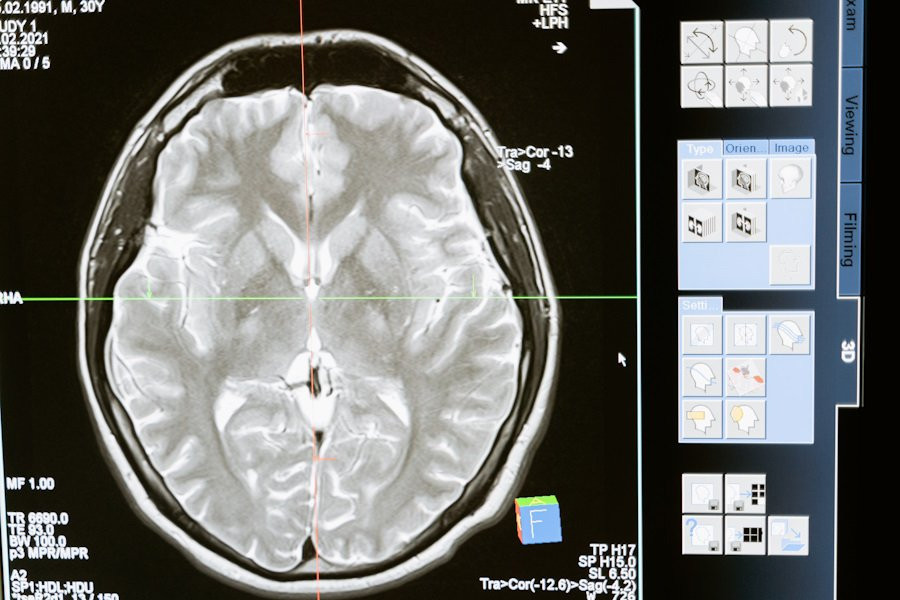

Нейробиологи РФ работают над созданием нейроинтерфейса, помогающем улучшить реакции у пожилых людей. Их исследования основаны на использовании транскраниальной магнитной стимуляции, или ТМС, сообщает ТАСС.

ТМС - это метод, при котором магнитные поля воздействуют на активные участки мозга. Этот метод может быть полезен в реабилитации после травм двигательного аппарата. Нейробиологи утверждают, что ТМС способствует активизации мозговой деятельности.

В ходе экспериментов исследователи усложнили задачу и использовали разные изображения кубиков. Направление граней определялось по их толщине. Согласно данным электроэнцефалограммы (ЭЭГ), магнитная стимуляция активных участков мозга привела к ускорению выполнения задач на 20%. Этот эффект продолжал сохраняться в течение полутора часов.